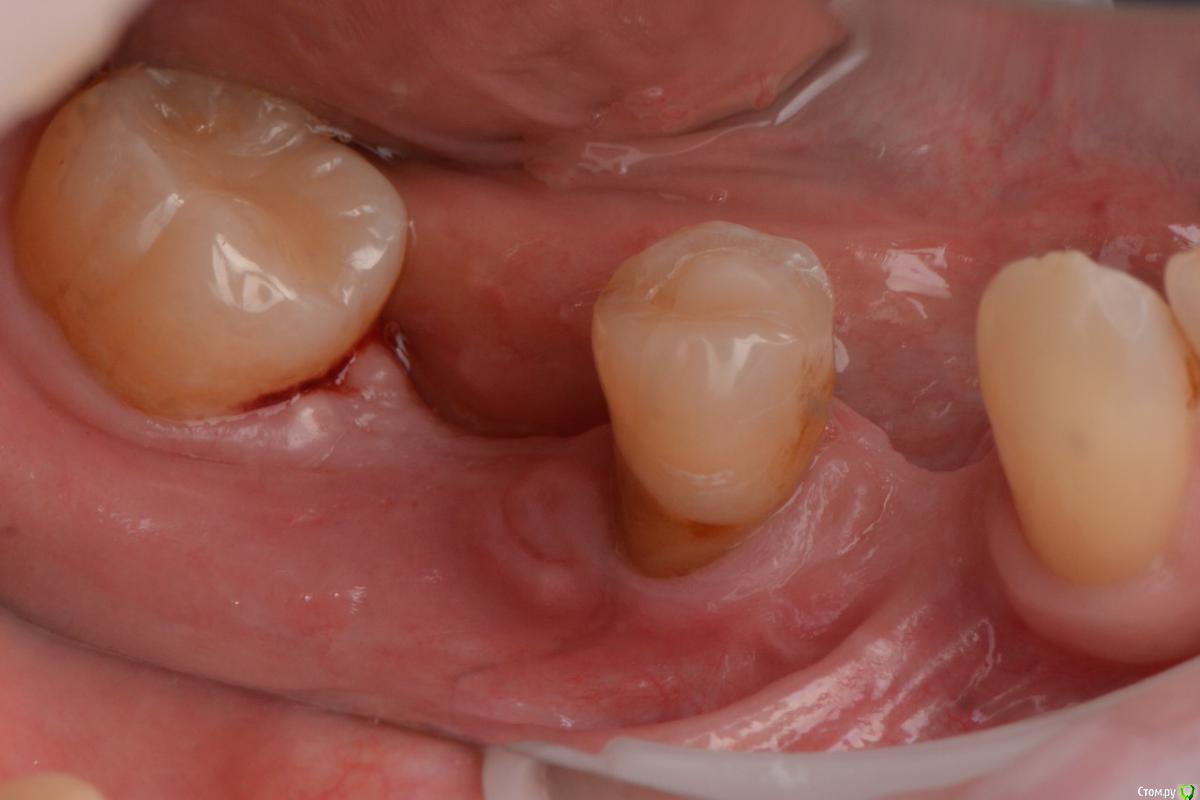

stommm Опубликовано 13 декабря, 2015 Поделиться Опубликовано 13 декабря, 2015 Всем доброго времени суток.Предыстория такая: в области 34 нкр с биооссом и биогайдом. В области 36 - биоосс+ауто+цитопласт, нагноение, долгие попытки вытянуть и в итоге ревизия и демонтаж мембраны. Отсроченно проведены установка имплантов и небольшое нкр в области 36. Десну по глупости сразу не добавил.Хочу перед расширением ЗПКД с помощью СДТ закрыть рецессию на 35. Вестибулярно думаю шансы неплохие, но дистально...? Планирую туннельный доступ через внутрибороздковый разрез. Как думаете. такого доступа хватит что бы завести и зафиксировать сст в области дистального сосочка? может сделать еще один небольшой разрез в области 36 и провести сст оттуда? Какие вообще шансы закрыть такую рецессию? Буду рад советам Ссылка на комментарий

Карен Аванесов Опубликовано 14 декабря, 2015 Поделиться Опубликовано 14 декабря, 2015 Могу ошибаться, но деменерализованный дентин корня, не способствует полноценному эпителиальному соединения, можно конечно жирный кусок сст подшить и все получится, но лучше просто дополнительно, потом, аккуратно "короновать" именно из-за демененрализованного (кариозного прости Господи) дентина. Ссылка на комментарий